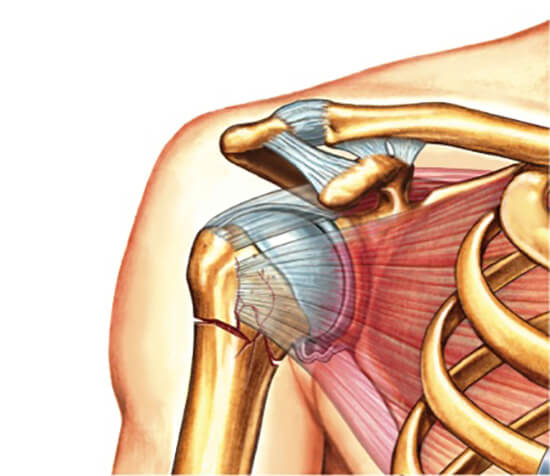

Шейка плеча — это проксимальная часть кости, на которую приходится около 6% всех переломов скелета у пациентов среднего и молодого возраста. Почти 50% суставных травм у пожилых людей связано с этой структурой. В 75% случаев переломы шейки плеча происходят у людей старше 60 лет. Женщины травмируются в два раза чаще, что связано с остеопорозом в постменопаузе. Проксимальная часть кости имеет тонкий кортикальный слой из-за возраста. В области хирургической шейки происходит переход к головке, где крепятся связки и мускулатура.

Основной механизм повреждения — падение на локоть или с опорой на вытянутую руку. Конечность может быть отведена, приведена или находиться в нейтральном положении при приземлении. При столкновении с поверхностью плечо выворачивается и отклоняется назад. Ударная сила смещает головку к суставной ямке, и она ударяется о лопатку или акромиальный отросток. В зависимости от положения руки различают три типа перелома: вколоченный, абдукционный и аддукционный.

Внутрисуставные травмы анатомической шейки встречаются редко и преимущественно у пожилых. Чаще перелом проходит через бугорки или под бугорками плечевой кости. Эти повреждения объединяются в группу переломов хирургической шейки плеча.